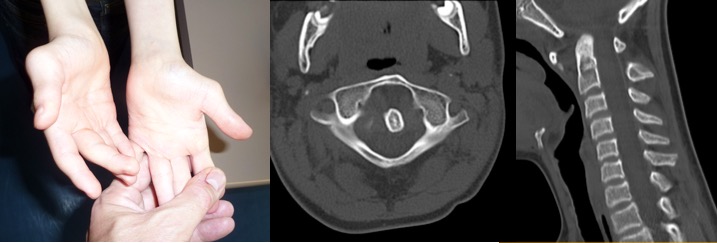

il peut s’agir d’une instabilité occipito-C1 ou C1-C2. Ces lésions font courir un risque important de déficit, de survenue chronique ou se décompensant brutalement, spontanément ou à la suite d’un trauma mineur (chute). il peut s’agir d’un atteinte ligamentaire (luxation C1-C2), d’un os odontoideum ou d’un ossiculum terminale.

il n’y a pas de consensus concernant l’intérêt d’un dépistage systématique chez les trisomiques. la question de la pratique des sports (ponney) est régulièrement posée, il semble approprié de réaliser des radios standard.